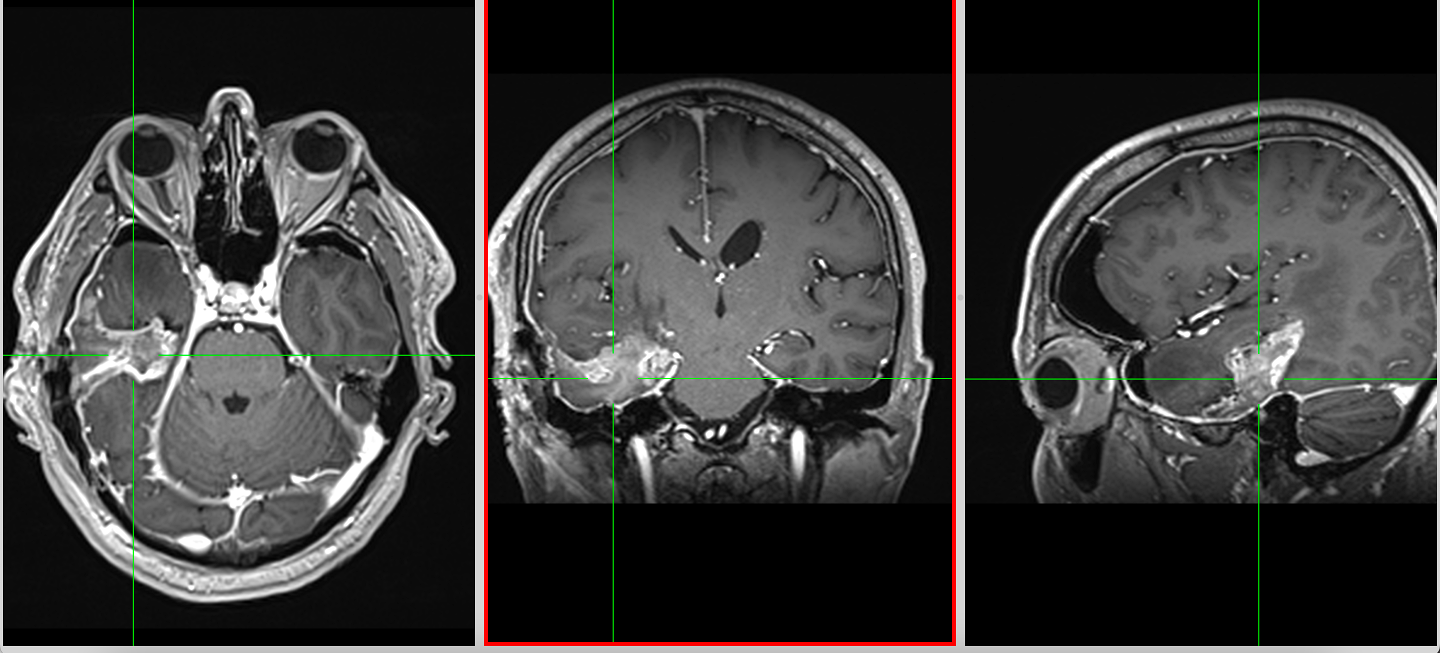

RMN-ul cerebral este standardul diagnostic, dar trebuie interpretat în context.

Pe lângă secvențele convenționale, tehnicile avansate aduc informații suplimentare:

- perfuzia evidențiază angiogeneza tumorală

- spectroscopia reflectă metabolismul celular

- DTI (tractografia) arată relația cu tracturile din substanța albă

Cu toate acestea, niciuna dintre aceste metode nu poate delimita complet infiltrarea microscopică. De aceea, planificarea chirurgicală și terapeutică trebuie să țină cont de această limitare.